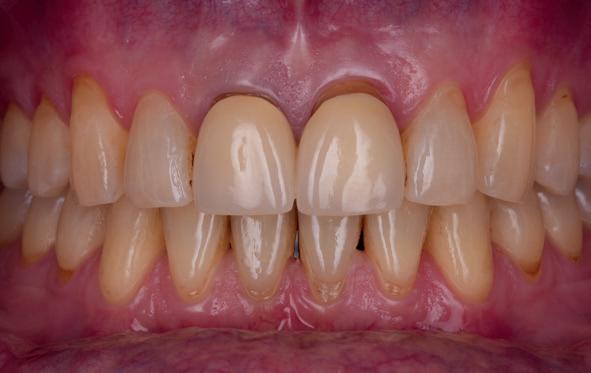

• Intra-orale scan voor studiemodellen, proefopstelling en beoordelen ruimte palatinaal

Vervaardigen essix retainer met dummies waarbij er een emergence profile van de 11 en 21 werd gevormd door eivormige dummies 4 mm in de gingiva te plaatsen

• Aanvulling zachte weefsels met de VISTA techniek en een vrij gingivatransplantaat uit het palatum links en direct dragen van de essix retainer

Na 4 weken intra-orale scan voor de etsbrug en kleurbepaling bij de technicus

• Plaatsen van de etsbrug met een composietcement

Voordat er gescand kon worden voor een etsbrug, werd een studiemodel vervaardigd om met de technicus te overleggen of er voldoende ruimte was voor 2 centrale incisieven in de mesio-distale zin en of er voldoende ruimte was in occlusie voor de vleugels van de etsbrug. Er hoeft enkel nog aan de 12 en 22 pala-

tinaal geslepen te worden als er geen 1,5 mm ruimte voor de vleugels behaald kan worden. De ruimte was op de dunste plekken 1 mm, dus een kleine preparatie in de 12 en 22 palatinaal was nodig. Omdat de kaak volledig afgevlakt was en dun was geworden, kunnen de dummies van de etsbrug enkel op de kaak “gelegd worden”, maar daarbij zijn er geen papillen en staat de cervicale rand van de dummies net voor de kaak. Een esthetisch resultaat kan daarmee niet behaald worden. Daarom is een aanvulling van de zachte weefsels in de breedte nodig, als het creëren van een emergence profile, waarbij het oogst alsof de gebitselementen uit het weefsel vertrekken.

Voor de aanvulling zachte weefsels chirurgie werd gekozen voor de VISTA techniek, hierbij worden er twee incisies partial thickness flap hoog in de mucosa gemaakt, waarna er ruimte vanuit de incisies wordt getunneld tussen de gingiva en het periost door middel van VISTA tunnel instrumenten. Uit het palatum links werd een vrij gingivatransplantaat geoogst van 15x10 mm met een dikte van 3 mm, die voor inhechten werd geëpithelialiseerd. Als het epitheel niet wordt verwijderd, kan deze graft door

de mucosa heen groeien, dat ten koste gaat van de esthetiek. In het donorgebied wordt een collageen spons ingehecht, waardoor de patiënt daar minder last van heeft. Het bindweefsel wordt door de hul-

pincisies met hechtingen naar het buccale en coronale deel getrokken en aldaar ingehecht. Met twee incisies werd ook de emergence profile gecreëerd (afbeelding 6-13). Voor een goede genezing van het

5. Beginsituatie voor behandeling

6. VISTA techniek twee hulp incisies

7. Vervaardiging tunnel met tunnelinstrumenten

8. Geoogst bindweefseltransplantaat uit palatum

9. Na de-epithelialiseren van transplantaat

10. Inhechten van een collageenspons in het donorgebied

11. Middels hechtingen het op de juiste plek trekken van het transplantaat

12. Transplantaat ingehecht

13. Occlusaal beeld verdikking van de zachte weefsels

14. Direct postoperatief plaatsen

van de essix met 2 dummy tanden

15. Twee weken post operatief

16. Creëren van een duidelijke indeuking in de mucosa voor emergence profile

17. Genezing van het palatum

18. Etsbrug frontbeeld

19. Etsbrug palatinaal